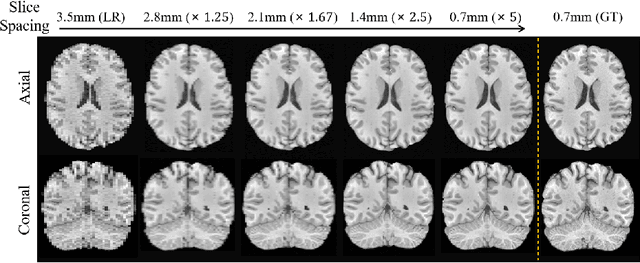

Abstract:Magnetic resonance (MR) images collected in 2D scanning protocols typically have large inter-slice spacing, resulting in high in-plane resolution but reduced through-plane resolution. Super-resolution techniques can reduce the inter-slice spacing of 2D scanned MR images, facilitating the downstream visual experience and computer-aided diagnosis. However, most existing super-resolution methods are trained at a fixed scaling ratio, which is inconvenient in clinical settings where MR scanning may have varying inter-slice spacings. To solve this issue, we propose Hierarchical Feature Conditional Diffusion (HiFi-Diff)} for arbitrary reduction of MR inter-slice spacing. Given two adjacent MR slices and the relative positional offset, HiFi-Diff can iteratively convert a Gaussian noise map into any desired in-between MR slice. Furthermore, to enable fine-grained conditioning, the Hierarchical Feature Extraction (HiFE) module is proposed to hierarchically extract conditional features and conduct element-wise modulation. Our experimental results on the publicly available HCP-1200 dataset demonstrate the high-fidelity super-resolution capability of HiFi-Diff and its efficacy in enhancing downstream segmentation performance.

Abstract:Magnetic resonance (MR) images are often acquired in 2D settings for real clinical applications. The 3D volumes reconstructed by stacking multiple 2D slices have large inter-slice spacing, resulting in lower inter-slice resolution than intra-slice resolution. Super-resolution is a powerful tool to reduce the inter-slice spacing of 3D images to facilitate subsequent visualization and computation tasks. However, most existing works train the super-resolution network at a fixed ratio, which is inconvenient in clinical scenes due to the heterogeneous parameters in MR scanning. In this paper, we propose a single super-resolution network to reduce the inter-slice spacing of MR images at an arbitrarily adjustable ratio. Specifically, we view the input image as a continuous implicit function of coordinates. The intermediate slices of different spacing ratios could be constructed according to the implicit representation up-sampled in the continuous domain. We particularly propose a novel local-aware spatial attention mechanism and long-range residual learning to boost the quality of the output image. The experimental results demonstrate the superiority of our proposed method, even compared to the models trained at a fixed ratio.